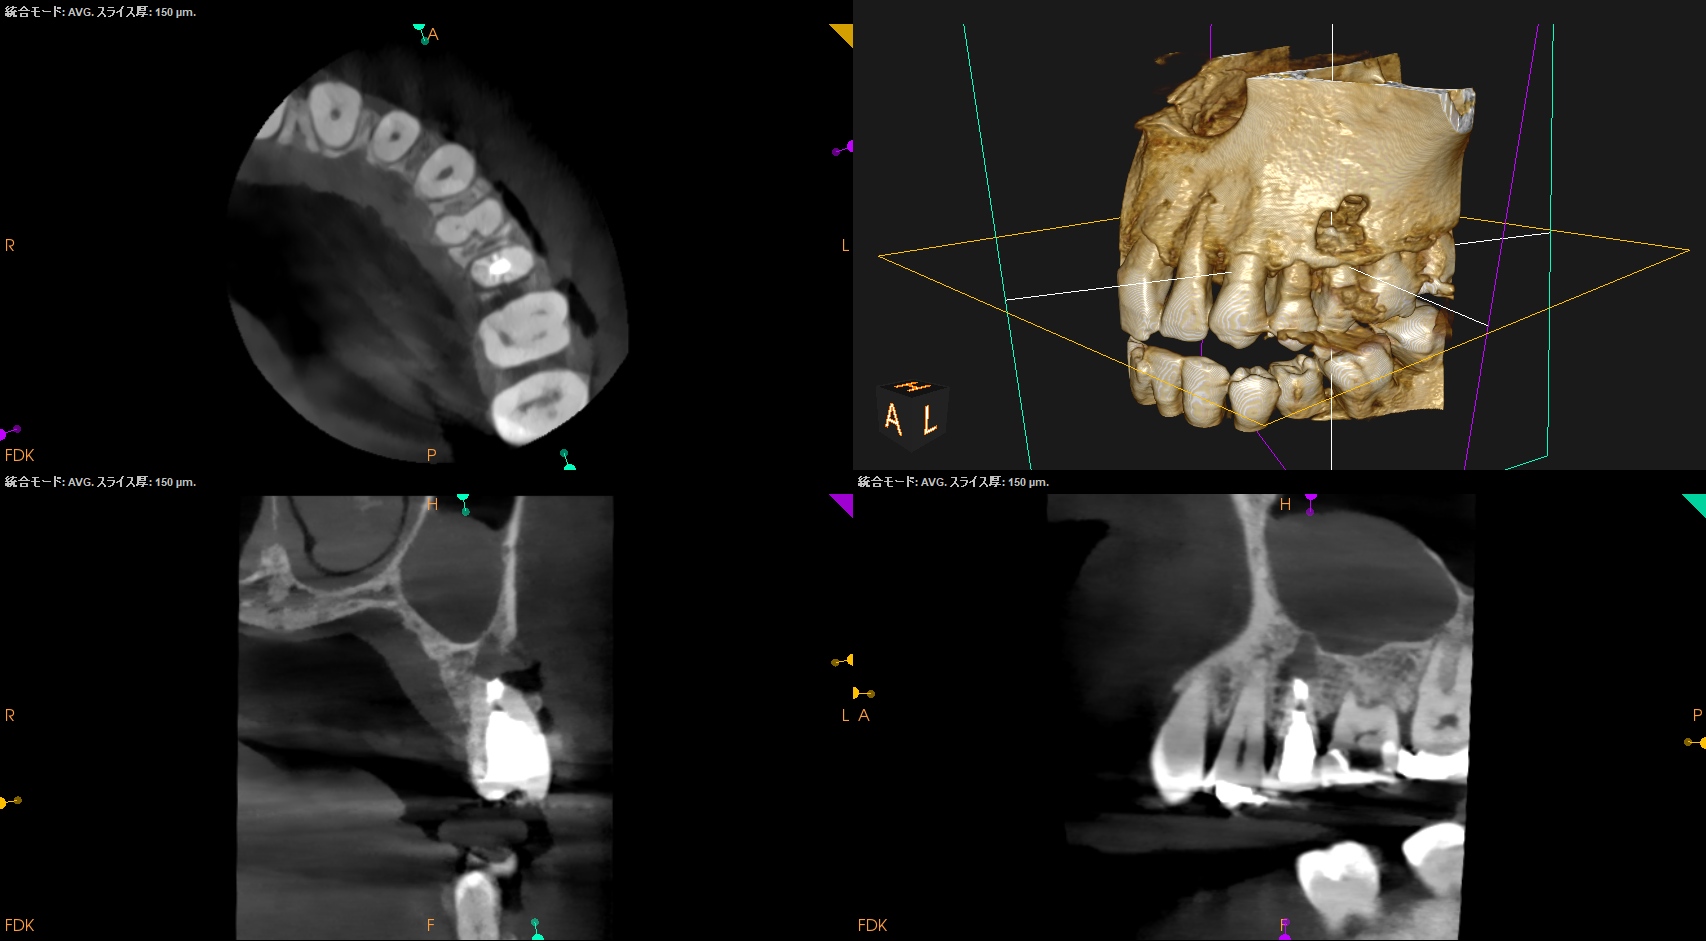

CBCTを撮影した。

CBCT(2024.5.21)

#13

上顎洞にApexが入り込んでいる#13が怪しい。

拡大すると、

#13のApexの根尖部の病変がSinus に入り込んでいる絵だ。

が、

根尖部は石灰化しており、

太く拡大形成済みである。

ということは…

Apicoectomyが必要だ。

その際は、

CEJよりも12.5mm下方にApexが存在し、

当該部分を2.6mm削合すると#13のApexが顔をだす。

ここから3mm下方で切断しようとすれば、頬側の皮質骨を2.4mm削合し、

歯根を3mmの幅削合する必要がある。